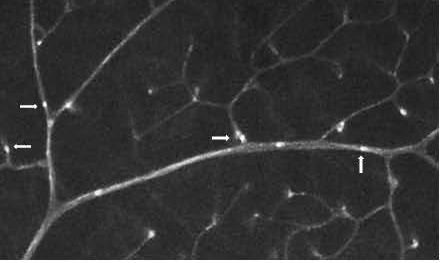

Leukostasis

Leukostasis, the adherence of leukocytes to endothelium, is a major component of non-proliferative diabetic retinopathy and is a general indicator of tissue inflammation. We measure retinal leukostasis by infusing animals with fluorescein-conjugated concanavalin A, flushing the circulation with buffer perfusion, carefully dissecting and flat-mounting retinas, and counting the number of leukocytes remaining in the lumenal space of blood vessels.